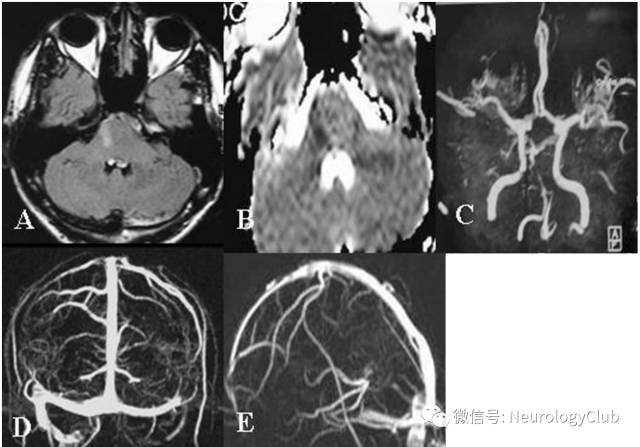

(图23:A-B:貌似急性脑梗死的右侧脑桥病灶;C:MRA可见基底动脉中段闭塞;D-E:MRV可见左侧乙状窦和颈内静脉远端以及直窦血栓形成